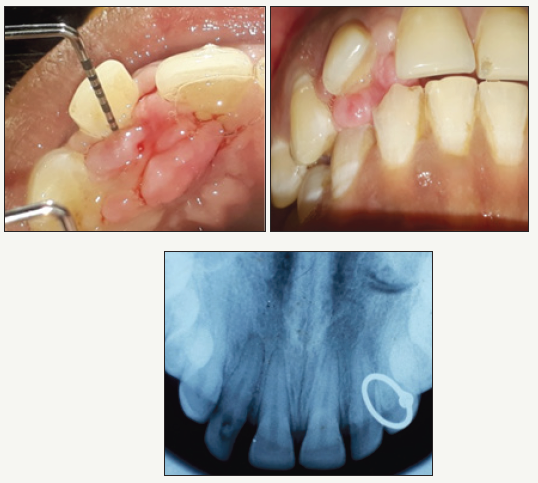

On extra oral examination, face was mesoprosopic, bilaterally symmetrical with a convex profile and incompetent lips. The regional lymph nodes were non palpable and non tender. Intraoral examination revealed solitary, non tender, reddish pink growth with lobulated surface on palatal gingival of maxillary central and lateral incisors. Local irritating factors like plaque and sub gingival calculus were present. Palatal pocket of 6mm was present irt#11#12 (FDI tooth notation) with gingival margin coronal to CEJ. Palpation revealed firm, fibrotic consistency with exudation from the pocket on pressure. There was pathological migration of #12 in labial direction and the tooth was grade I mobile and tender on percussion (Figure 1).

figure 1:

IOPA revealed loss of interdental bone in the maxillary right anterior region and widening of periodontal ligament space irt#12 with developing periapical radiolucency. Blood examination included haemoglobin, bleeding time, clotting time and complete blood count which were found within normal limits.

On macroscopic examination, the biopsy yielded a 12mmΧ10mm large pale pink mass with lobulated and corrugated surface and firm-rubbery consistency (Figure 2).